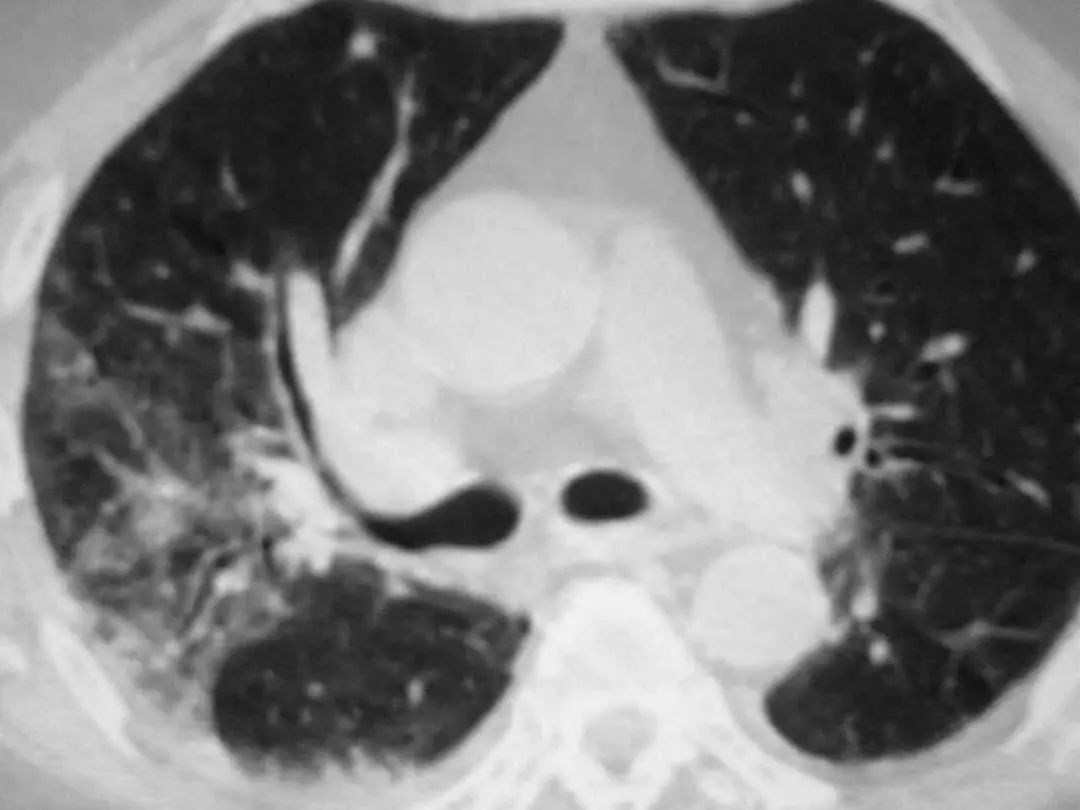

图1.4 53岁的严重军团菌肺炎患者。胸片显示双肺下叶致密实变。

图1.7 CT扫描显示左下叶模糊的气腔浸润。